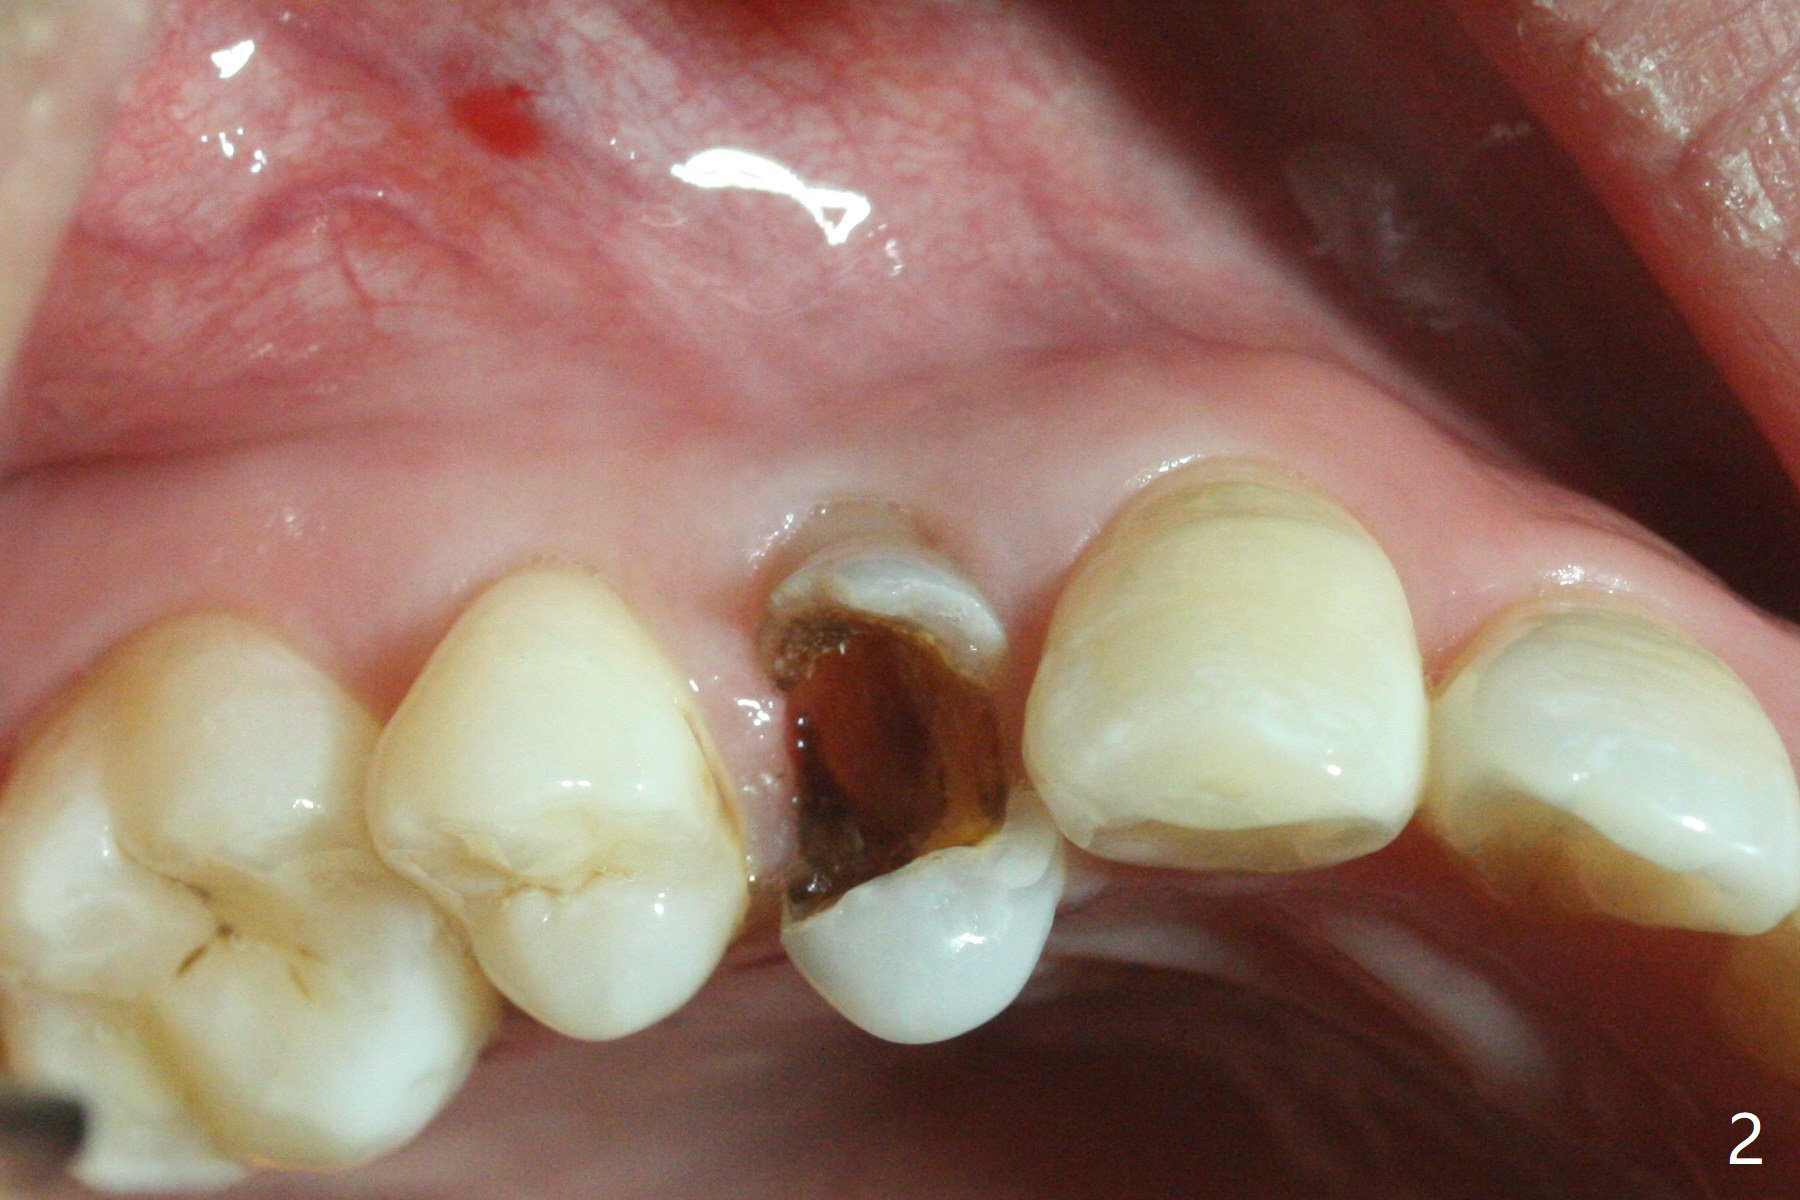

今天临床实践让我对植骨概念和操作有两方面突破,与大家分享讨论。PRF/sticky bone(粘性骨粉)以及血小板因子(成品)对软硬组织缺损修复重建无疑起到不可缺少作用。但是大多数拔牙病例并不是那么严重,放置骨粉和覆盖胶原膜足够了。为了避免费时的缝线固定胶原膜,介绍一种简易固定方法,助手可以做。31岁女不想保留严重龋坏右上4(图一至四,拍摄临床照片,与后期比较,但愿简易植骨不产生骨板塌陷),虽然术前根尖片显示根尖阴影(图四),术中没有根尖骨板缺失。估计没有严重骨板缺损,她又年轻,再生能力强,所以做简易植骨(异体骨,图五),也就是不需要PRF或者血小板因子,骨粉表面放置GEM CAP(9-12月吸收膜),由胶水固定(图六),在放置牙周敷料前,在胶原膜表面涂一层含有抗单纯疱疹病毒凡士林(图七),但愿敷料脱落时,不至于把胶原膜带下来。术后第六天,病人由于左上第二磨牙不适回来,说敷料脱落,没有不适,要求检查,其实膜也丢失(图八,九),骨粉好像挺稳定,没有做如何处理,尽管少量骨粉离开牙槽窝(<)。